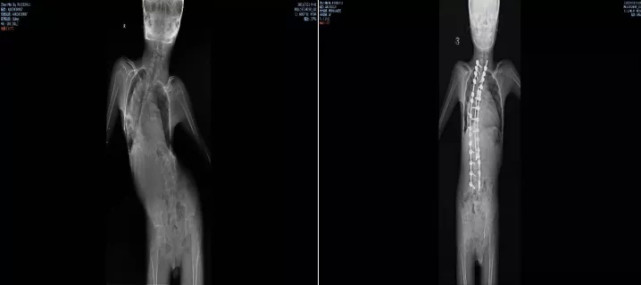

图片图/手术前后对比图 来源/ 受访者供图

脊柱的扭曲,增加了寻找药物的鞘内注射点,让药物顺利椎管内的难度。儿科接诊后反复与各科室沟通,最终决定让小乐先接受脊柱畸形矫形手术治疗。

2021年9月,李淳德在完成脊柱畸形矫正手术的同时,还要切除部分腰椎椎板,为后面注射药物预留出骨性通道。虽然手术顺利,但术后小乐的腰部无法弯曲,已经没有同正常人一样的解剖标志,预留的通道也很难找到。麻醉科副主任胡晓通过超声引导反复摸索,寻找到预留的骨性通道,最终穿刺成功,完成国内首次SMA脊柱畸形矫形术联合诺西那生鞘内注射。